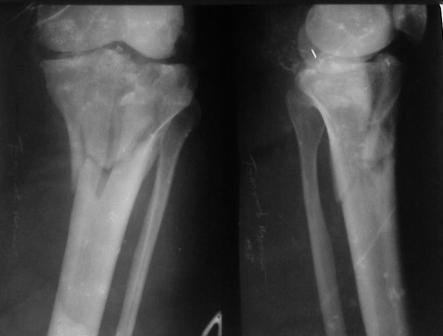

Обратился больной 46л. 3-месяца назад в каком-то городке Дальнего Востока упал с высоты, сделана Р-графия, наложена гипсовая повязка, от предложенной операции отказался и уехал домой, дальше где и как лечился, не говорит.

Ходит при помощи двух костылей, жалобы на боли при нагрузке, в покое и при движении, без нагрузке боли нет, разгибание 175 гр, сгибание 90 гр, симптомов повреждения связочного аппарата к/с не определяется, от предложенного артродеза пока отказывается.

По тактике лечения, более импонирует второй вариант, но наружная плато расколота и туда при нагрузке внедряется н/мышелка бедра, поэтому после дистракции как репонирвать: или стяжными винтами, или изогнутами спицами или субхондральная костная пластика?

У пациента основной проблемой является импрессионый перелом наружного мыщелка, уже неправильно сросшийся, по-видимому. Аппаратом закрыто можно только подправить угол на уровне метадиафиза. Что

улучшит разве что внешний вид конечности, но не решит основной проблемы - грубой деформации суставной поверхности.

Перелом сложный, особенно через 3 месяца. Артродез всегда успеете сделать.

Но по моему мнению, все-таки возможно проведение открытой репозиции.